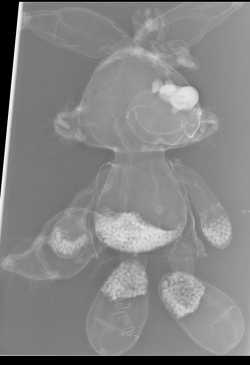

Erst das Kuscheltier - dann das Kind

Kinder kommen oft sehr ängstlich mit Kuscheltieren oder Puppen zum Röntgen. Um den Kindern diese Angst zu nehmen, kann man vor deren neugierigen Augen, zuerst die kuscheligen Begleiter unter die Röhre legen.

Spätestens wenn die Kinder die Bilder Ihrer Kuscheltiere sehen ist die Angst vorm Röntgen meist vergessen. So wie bei den unten abgebildeten Bildern.